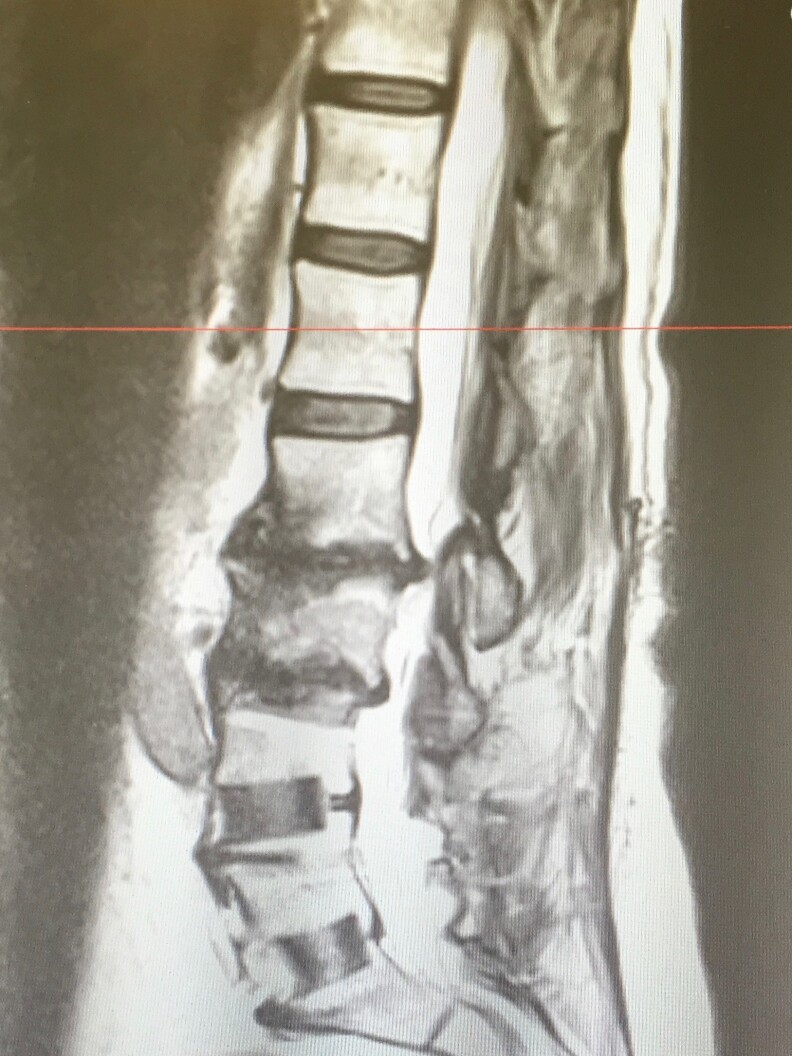

By her mid-50s, she had two back surgeries and both her hips replaced.

Germanovich says he sees lots of patients like Curtis, middle-aged men and women whose bodies are naturally deteriorating. He says it’s no wonder that middle-aged people are dying of opioid overdoses at the highest rates in California. They’re the ones most in need of pain relief.

"Degenerative neck and back disease typically starts to come right after the age of 45," he says, "and doesn't manifest itself in big ways until someone is almost 50."

Last year, Curtis had yet another surgery, this time for degenerative disc disease. It has given her some relief. Since that surgery, Germanovich has been helping her taper off opioid pain relievers.